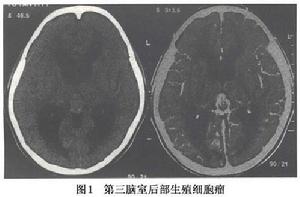

4.MRI檢查 MRI對顯示鞍上小的生殖細胞瘤(直徑<1cm)或脊髓轉移灶十分清楚;顯示松果體區生殖細胞瘤常為圓形、橢圓形或不規則形多數T1為等或稍低信號,T2為稍高信號,少數亦可為等信號;注藥後均勻一致的強化,邊界清楚有時少數僅呈中度或不均勻強化有報告20%~58%的生殖細胞瘤有小的囊變,這些囊變由於蛋白性液體或壞死液化所致,通常極小,有時在瘤內有小出血灶,在T1像為高信號;松果體區者可侵犯中腦和丘腦在T2像上有周邊模糊高信號影。MRI對腫瘤的種植或播散顯示全面除了T1及T2像的多發病灶顯示清晰而注藥後病變明顯強化。底節生殖細胞瘤也是T1等或低信號而T2稍高信號,注藥後可均勻強化有的顯示同側皮層有萎縮現象。